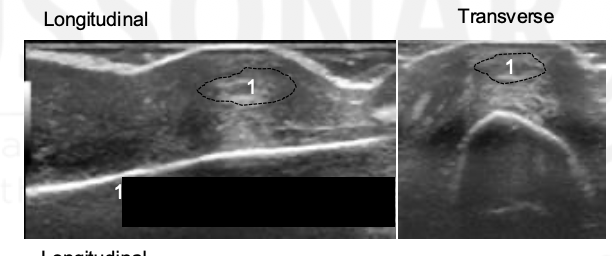

What grade is the synovial hypertrophy?

Grade 0

Grade this synovial hypertrophy

Grade 1: minimal within imaginary line between joint edges

Grade 2: moderate, extends over joint line with concave appearance

Grade 3: severe, extends beyond joint line with convex appearance